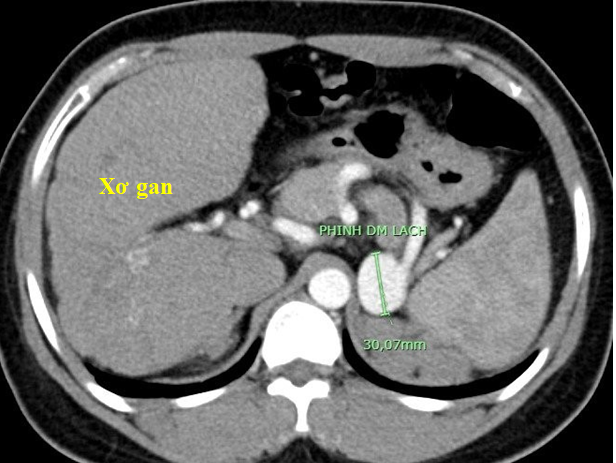

Qua chụp cắt lớp vi tính 128 dãy ổ bụng có tiêm thuốc cản quang đã phát hiện cùng lúc nhiều bệnh lý bên trong ổ bụng bao gồm: xơ gan điển hình, khối u thận kích thước lớn, túi giả phình nhánh động mạch thận và khối phình động mạch lách.

Hình ảnh xơ gan và phình động mạch lách trên phim chụp cắt lớp vi tính 128 dãyHình ảnh xơ gan và phình động mạch lách trên phim chụp cắt lớp vi tính 128 dãy

Thật bất ngờ, sau khi chụp phim, sử dụng các kỹ thuật tái tạo ảnh và dựng hình hiện đại, các bác sĩ còn phát hiện nhiều bệnh lý phối hợp bên trong ổ bụng của người bệnh, bao gồm: (1) xơ gan điển hình, (2) khối u thận phải kích thước lớn (u mạch cơ mỡ, kích thước 8,5 x 6,5 cm) và có túi giả phình nhánh động mạch thận nuôi khối u (1,9cm), và (3) khối phình động mạch lách kích thước lớn (3,0 cm).